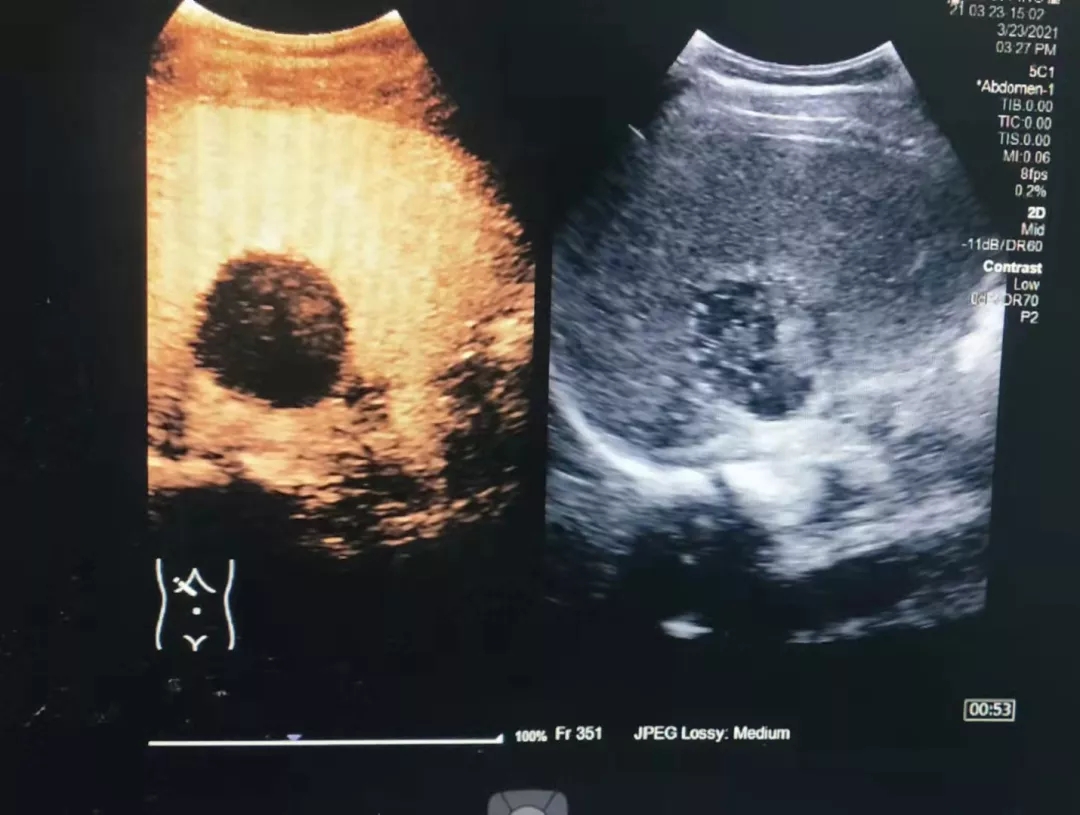

自我院功能检查科成功开展市内首例超声造影检查技术后,近期又开展了多例脏器(包括肝脏、甲状腺、乳腺、淋巴结等)超声造影术。该技术的全面成熟开展,标志着我院超声造影检查技术再上新台阶,必将进一步推动陇南地区超声医学专业的发展。

图为开展的肝脏超声造影检查

目前国内普遍成熟使用及我院使用的超声造影剂为六氟化硫微气泡(声诺维),它是由惰性气体构成的2-5微米的微气泡,是纯血池造影剂,不进入组织间隙,其经外周静脉注射后,可通过肺循环到达全身各脏器及组织,检出低流量、低流速的血流信号,显示正常组织和异常组织的灌注差异。数分钟后微泡破坏,随呼吸排出。